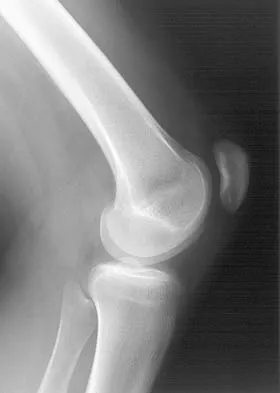

Figures 4a through 4c show the radiographs of a 43-year-old woman who sustained a twisting injury to her right ankle. She has ankle pain and tenderness medially and laterally. To help determine the optimal treatment, an external rotation stress radiograph of the ankle is obtained. This test is designed to evaluate the integrity of what structure?

In the presence of a supination external rotation-type fracture of the distal fibula (Weber type B), stability of the ankle is best assessed by performing an external rotation stress AP view of the ankle. This test is used to assess the integrity of the deltoid ligament. The presence of a deltoid ligament rupture results in instability and generally is best managed surgically. The gravity stress test can also be used. Egol KA, Amirtharajah M, Tejwani NC, et al: Ankle stress test for predicting the need for surgical fixation of isolated fibular fractures. J Bone Joint Surg Am 2004;86:2393-2398. McConnell T, Creevy W, Tornetta P III: Stress examination of supination external rotation-type fibular fractures. J Bone Joint Surg Am 2004;86:2171-2178.